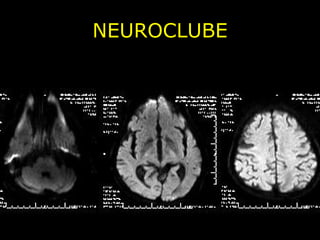

NEUROCLUBE CASO 1

NEUROCLUBE